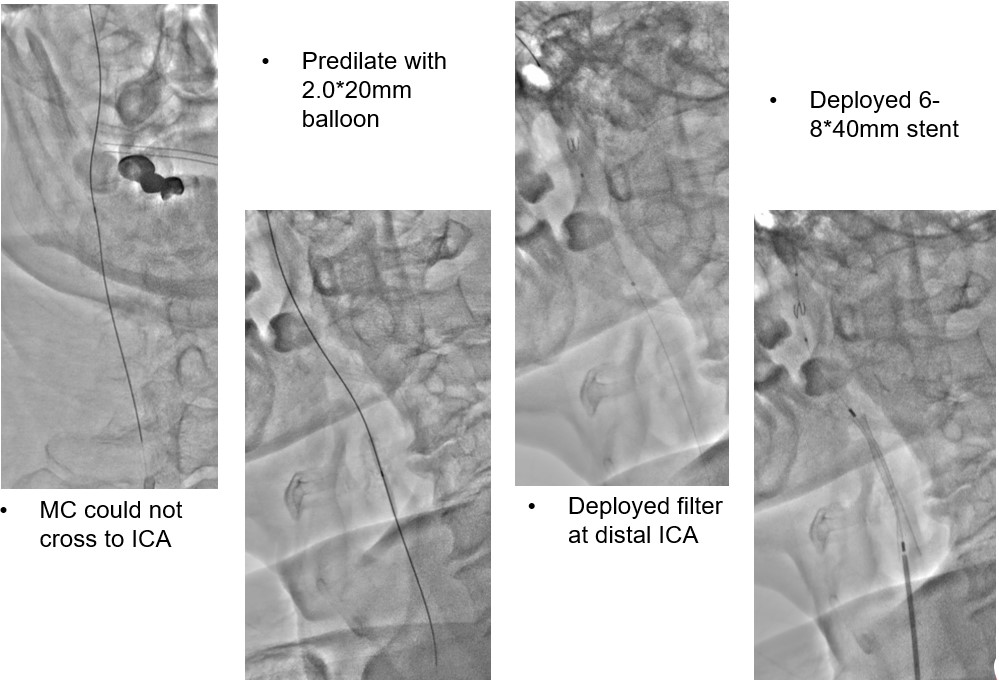

We tried wiring to left ICA occlusion with microcatheter first but failed.Then we tried PTA for right CCA occlusion. With microcatheter support, Gaia 2nd wire advanced to right ICA difficultly2.0mm small balloon pre-dilateddistal filter placement then carotid stenting smoothly.Patient symptoms improved dramatically and discharged 4 days later.We tried elective PTA for right SFA CTO by bilateral puncture approach. Antegrade from left transfemoral cross over sheath, and retrograde from right POPA.Antegrade failed wiringThen retrograde wire successfully advance to antegrade microcatheter -> Rendezvous -> externalization -> balloon pre-dilate and stenting

Familial hypercholesterolemia may cause poly-vascular atherosclerotic diseases (triple vessel CAD, PAOD, bilateral CCA occlusion in our case)Decision of choice for revascularization in bilateral CCA total occlusion is importantEndovascular treatment for CCA-ICA occlusion is controversial and also challengeDistal ICA filtering and carotid stenting is a treatment of choice and can be considered if other treatment option unavailable